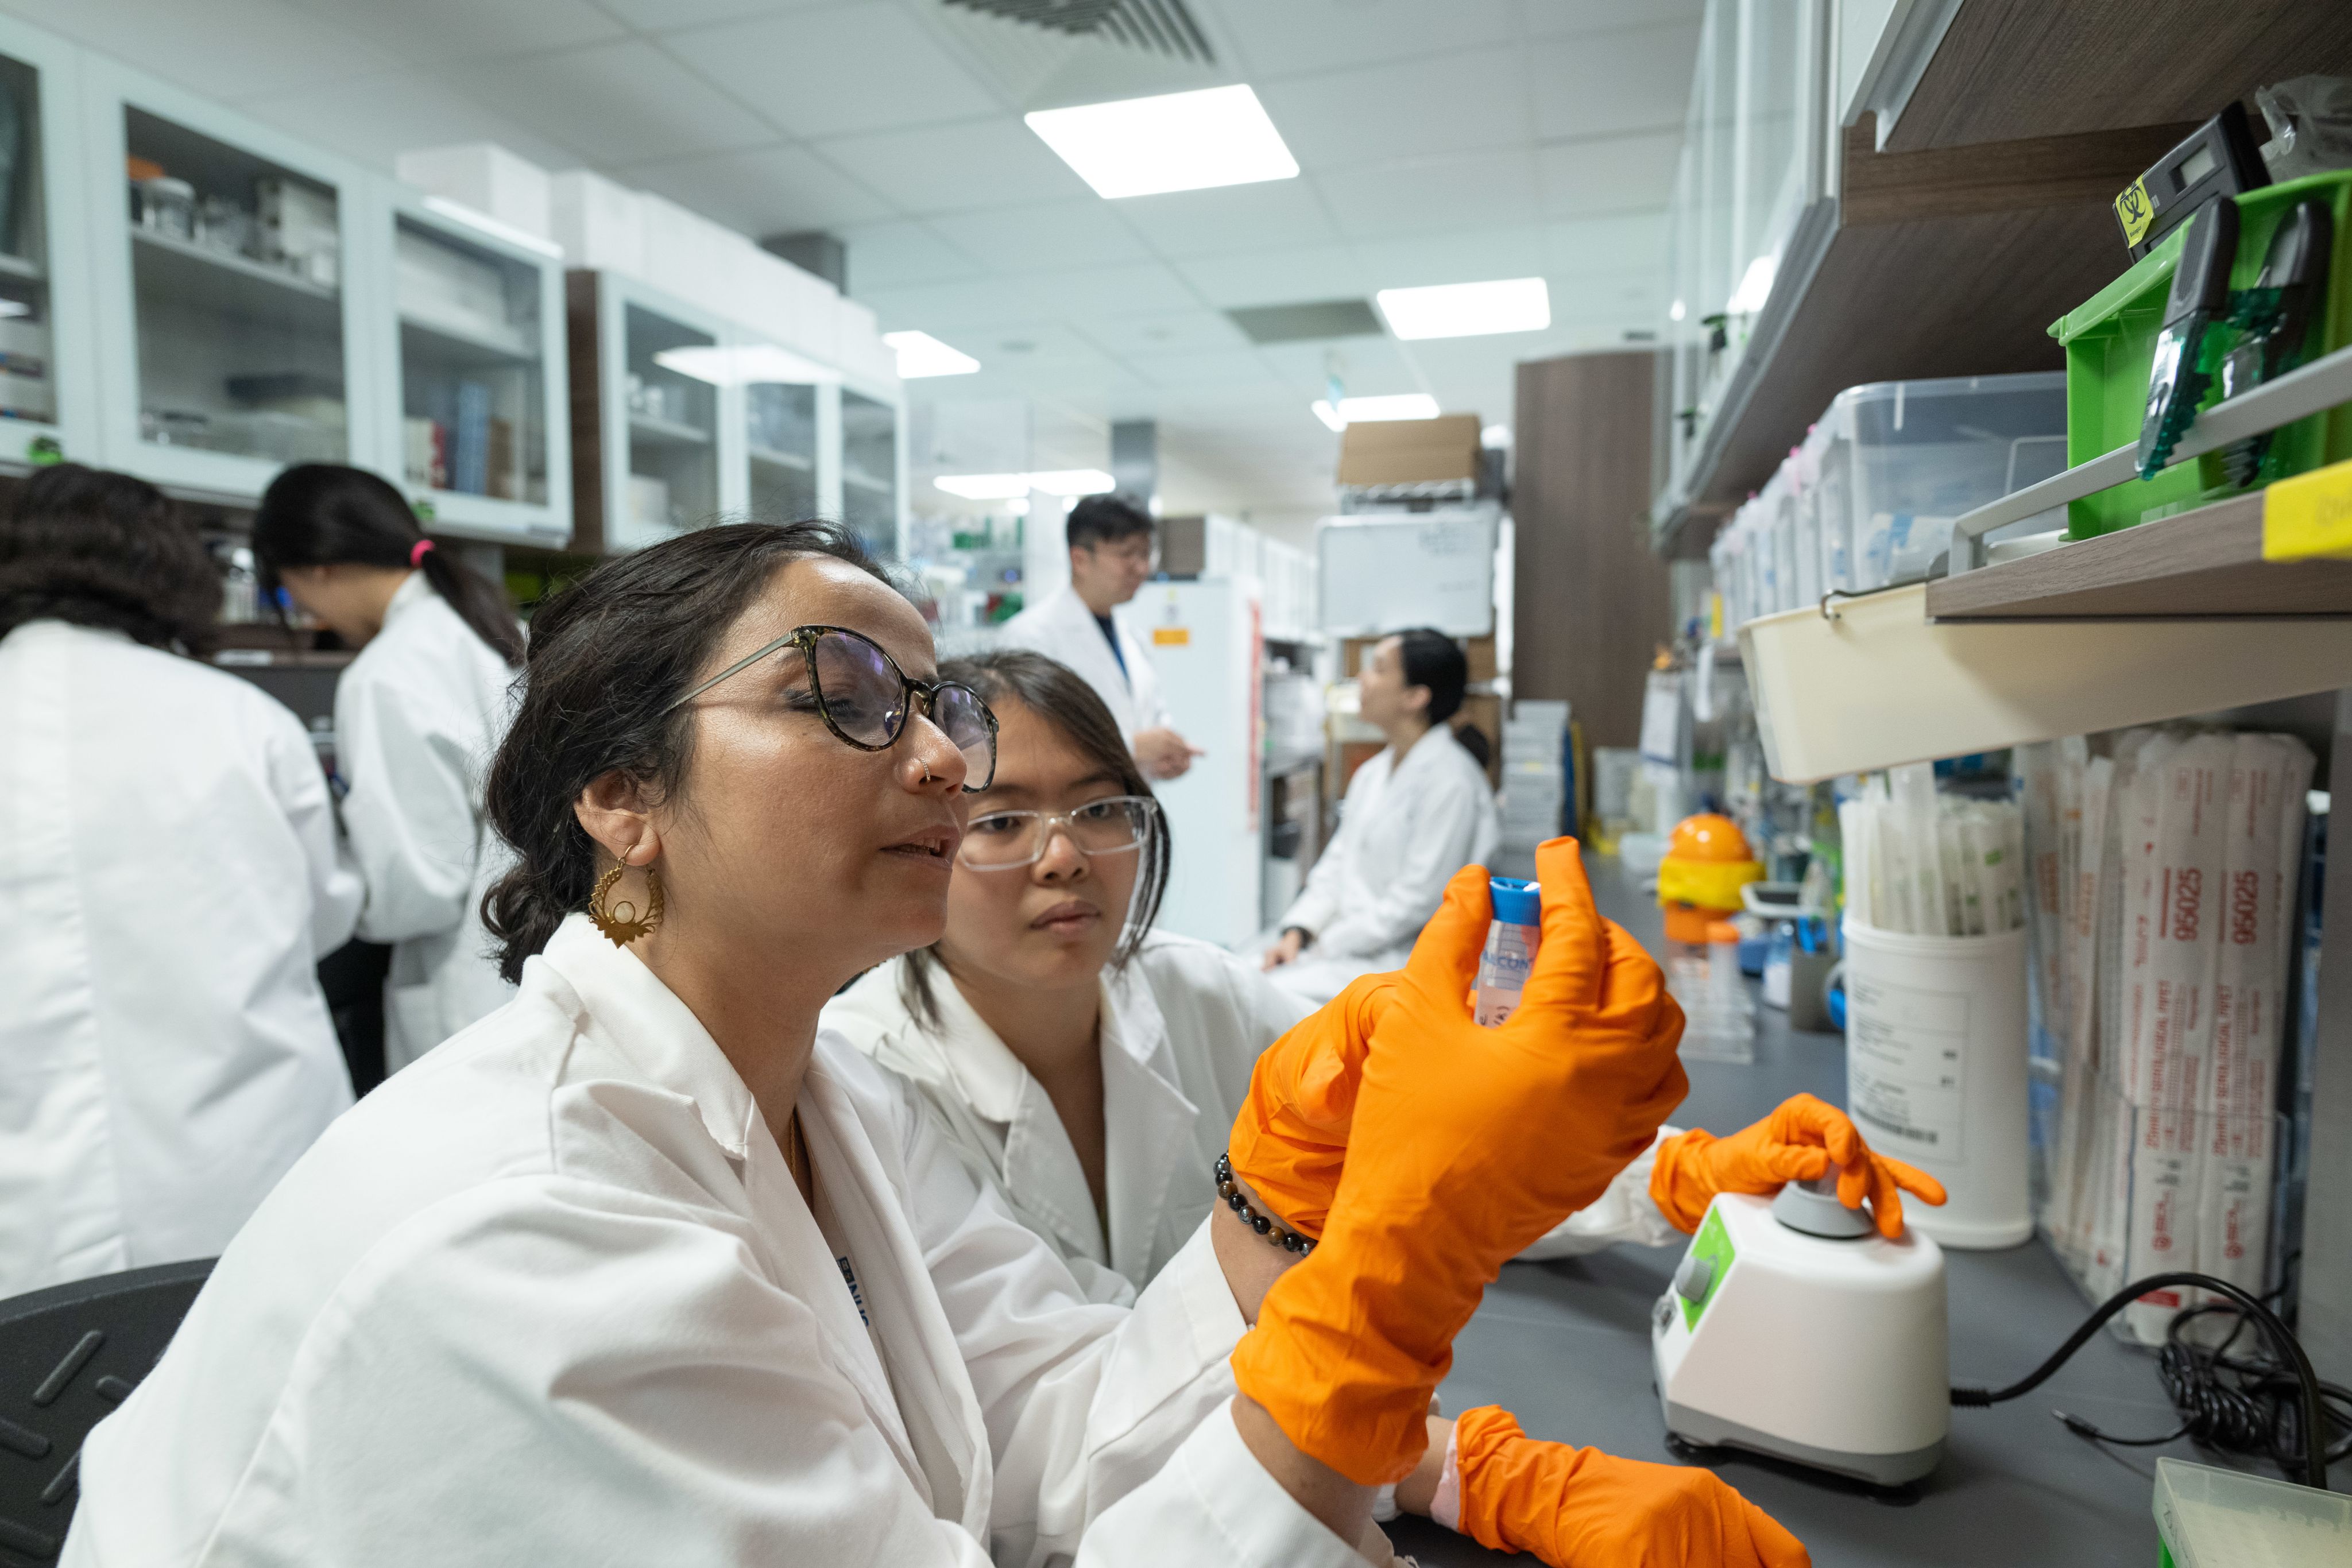

“What we know about reproductive aging, and the impact it has on a woman, is so limited,” said Zhongwei Huang, a consultant in the Department of Obstetrics & Gynaecology at Singapore's National University Hospital and deputy director of the Bia Echo Asia Centre for Reproductive Longevity and Equality (ACRLE).

ACRLE, which opened in Singapore in 2021 with an $8 million gift from the Bia-Echo Foundation, founded by U.S.-based lawyer and entrepreneur Nicole Shanahan, is one of a small but growing number of organizations in Asia trying to decipher the female reproductive aging process.

Huang’s team, a group of around 20 researchers from across the world, uses a mixture of lab-based research, human trials and population modeling to identify the biomarkers of reproductive aging by observing changes in blood and tissues.

Huang's team is looking for the biomarkers of female reproductive aging. (Photo: Weixiang Lim)

Huang's team is looking for the biomarkers of female reproductive aging. (Photo: Weixiang Lim)

One problem holding research back is that “there’s so little data available on Asian populations,” Huang said. Women of Asian descent have long been excluded from major menopause studies, he added, partly due to a longstanding, now de-bunked, myth that Asian women do not suffer from menopausal symptoms.

The highly personalized nature of menopause – symptoms and severity vary from woman to woman – makes large-scale data collection vital for developing new treatments, Huang added.